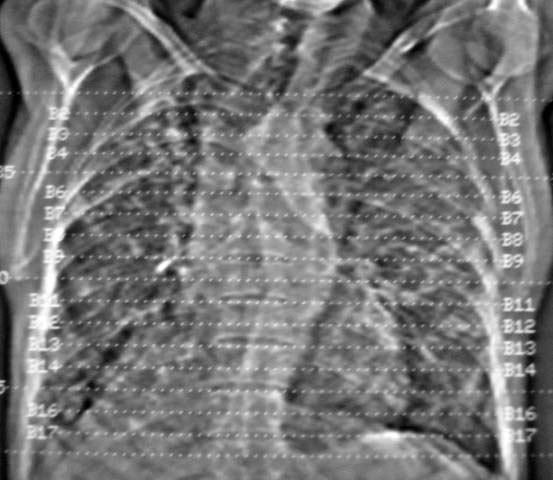

男,85岁,发热2月, 血常规:hgb99g/l.rbc2.55×1012/l.wbc3.8×109/l.n78.2%  l20.7% m1.1%.  hct26.3% .血沉20mm/hg.痰检结核杆菌阴性。ddp阳性。痰少粘稠色白。无咳血。

1.右上肺陈旧性肺结核灶;

2.左上肺、双下肺及右中叶肺炎(左上肺肺炎治疗后好转)

双肺继发型肺结核,肺纤维化,肺气肿,胸膜肥厚黏连。